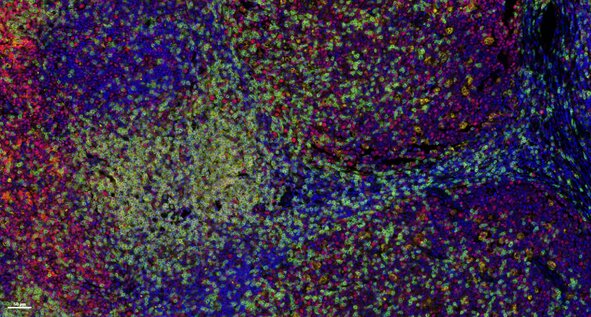

Multiplex immunofluorescence (mIF) is a powerful technique that allows researchers to simultaneously visualize and analyze multiple components of the tissue microenvironment. Multiplexing uses multiple antibodies with fluorescent detection to target specific proteins within the microenvironment, allowing researchers to create a detailed map of the various cells, proteins and their interactions. We offer both low plex and high plex options for mIF which allow you to profile tissues to determine cell phenotypes, their functional state, and cell interactions.